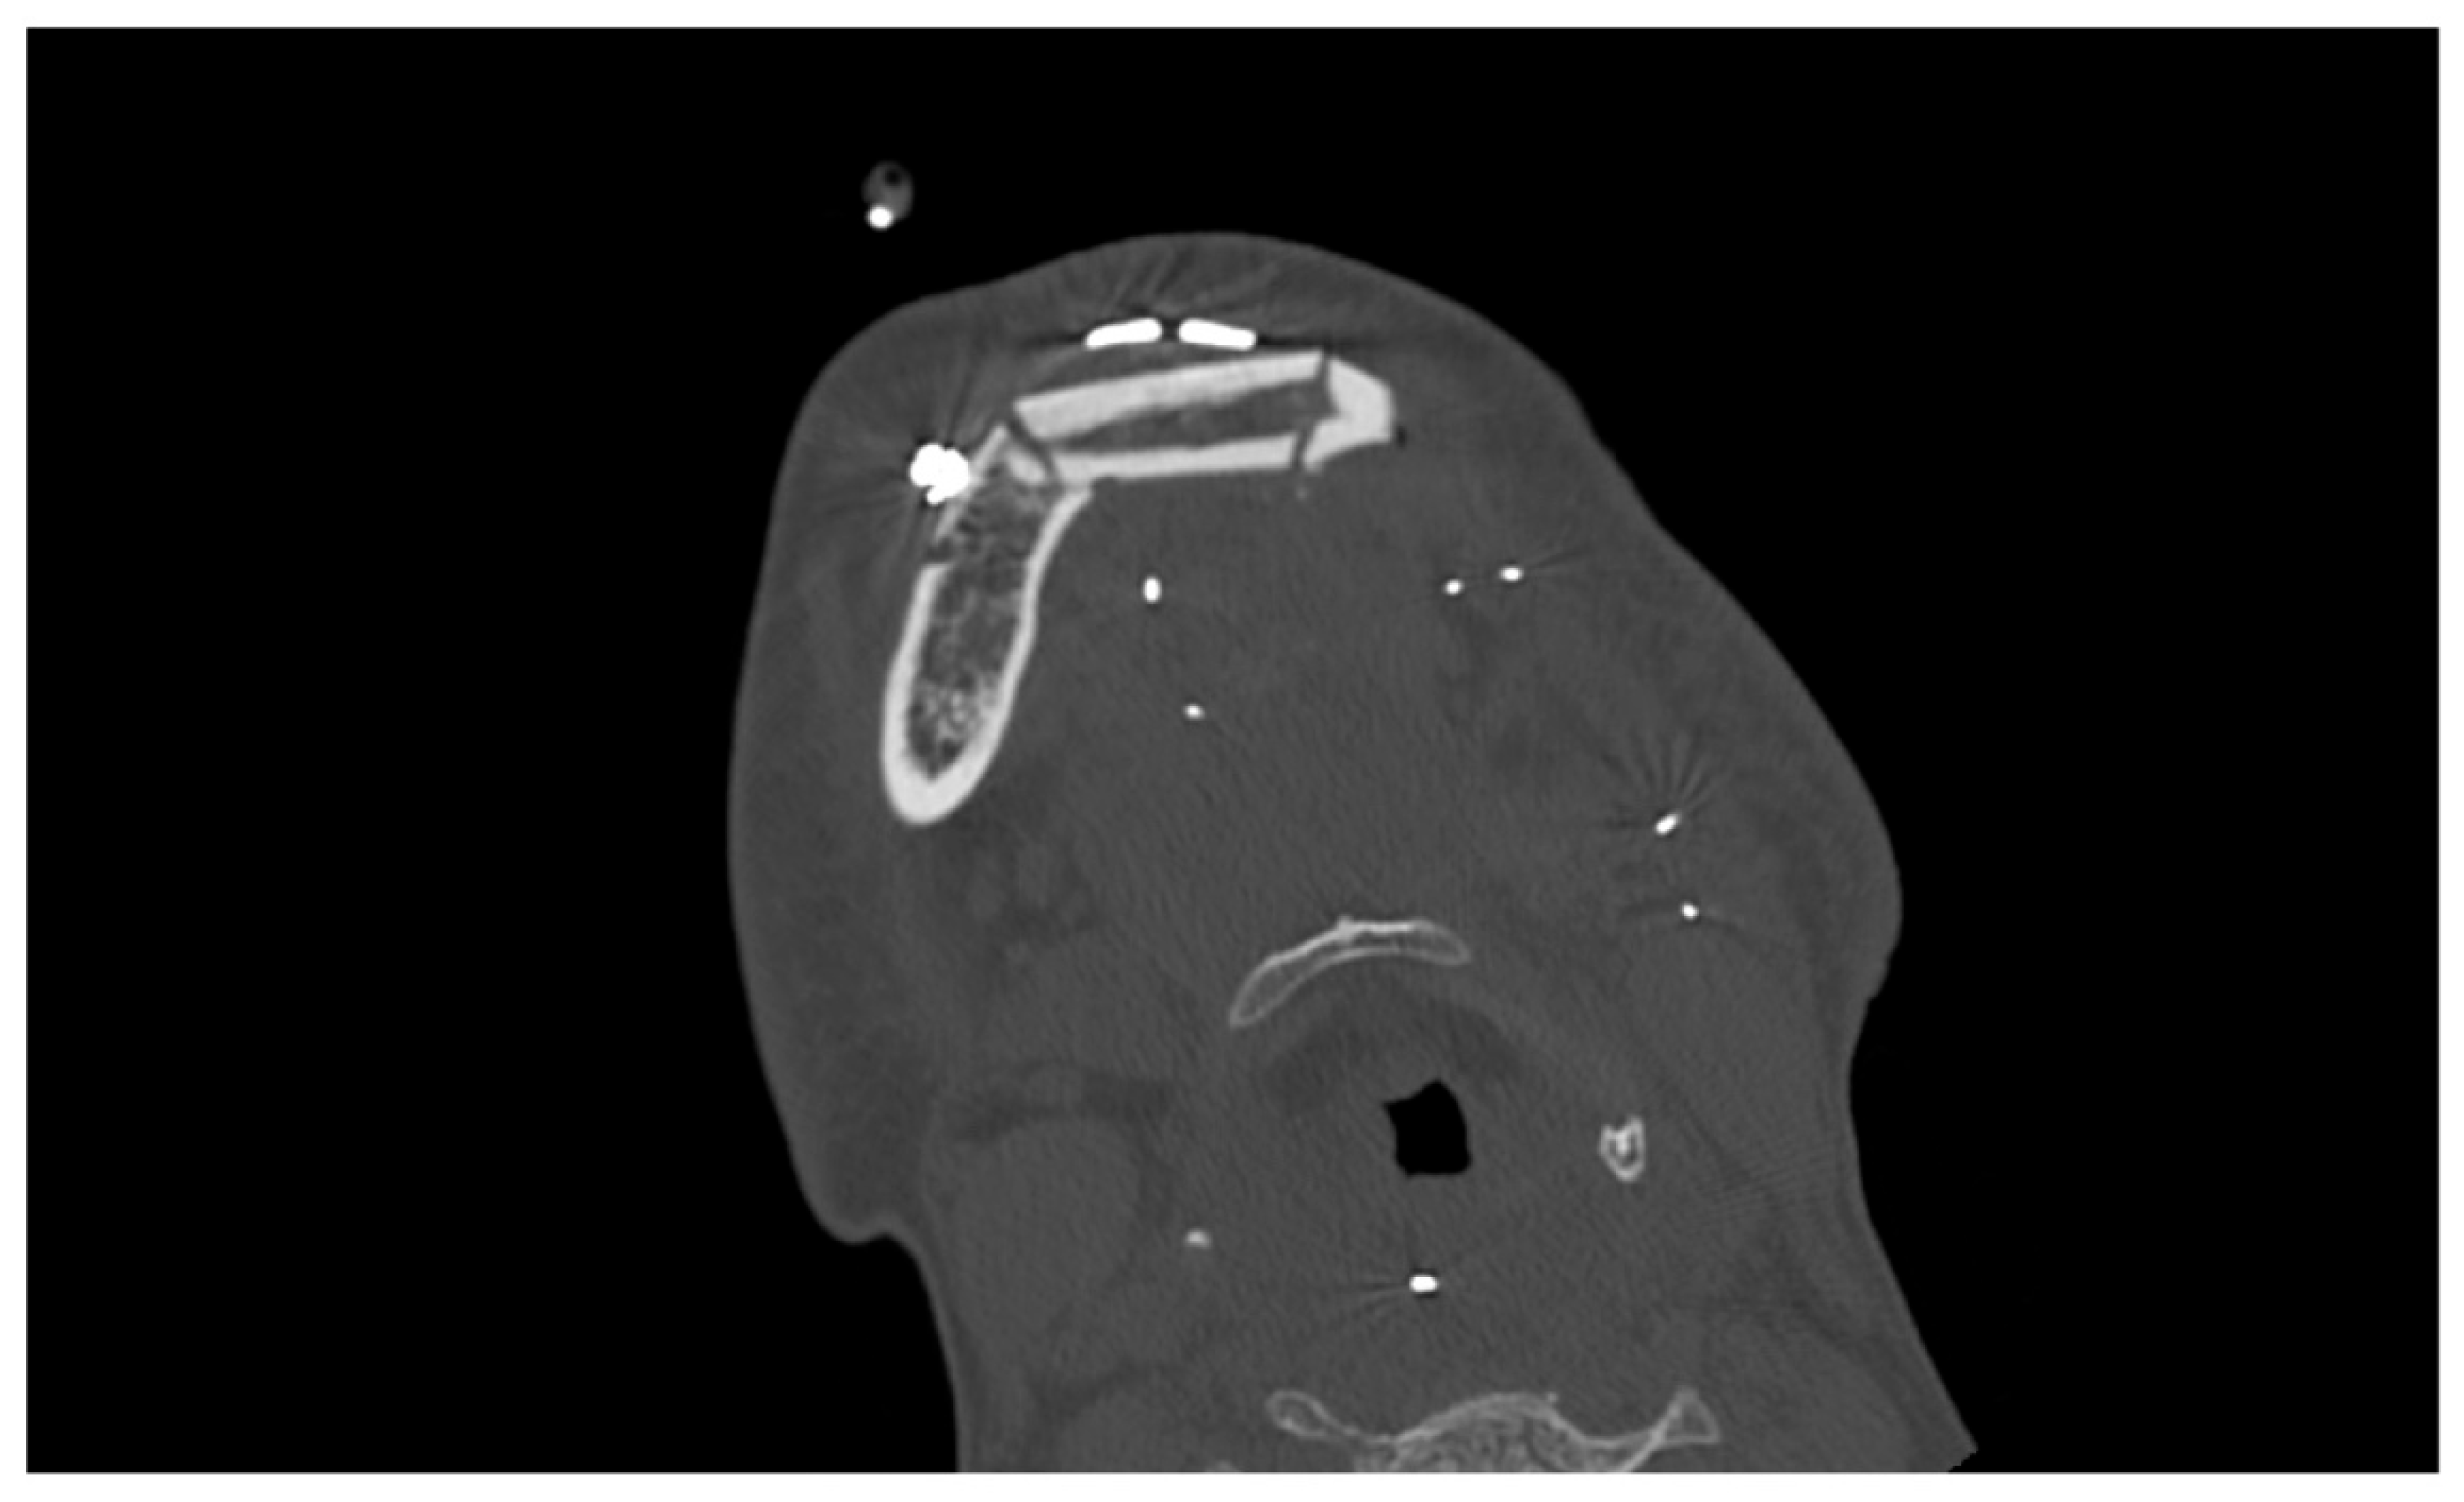

The pulp vitality test (cold test) was positive for the elements 3.2–3.3–3.4–3.5 and 3.6, and no pathological pocket probing depth was detected in any of the involved teeth. The bi-dimensional OPG showed a wide radiolucent lesion, located between the canine and second premolar on the left side of the mandible. The second level tri-dimensional imaging CT scan (axial tomography) showed a radiolucent mass in the left mandibular body, with erosion of the mandibular cortex. The two-dimensional and three-dimensional imaging findings are presented in Figure 2.

Figure 2.

OPG (A) and CT (B) radiological findings.

A diagnosis of ameloblastoma was suspected based on these imaging findings, considering its typical radiological features and localization.

The surgical procedure was successfully completed with no immediate complication. One week after surgery a CT scan was performed for post-surgical follow-up (Figure 4).

Figure 4.

Radiographic appearance of the fibula flap and buccal osteosynthesis plate.